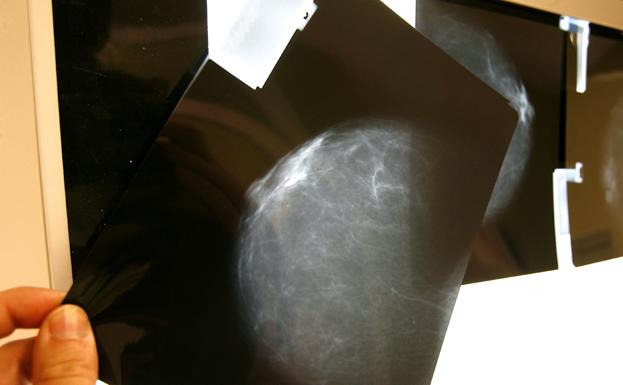

Los investigadores aislaron y reactivaron células T específicas del cáncer de una sola paciente cuyo tumor de mama estaba en estado de metástasis y las células reactivadas eliminaron todas las lesiones